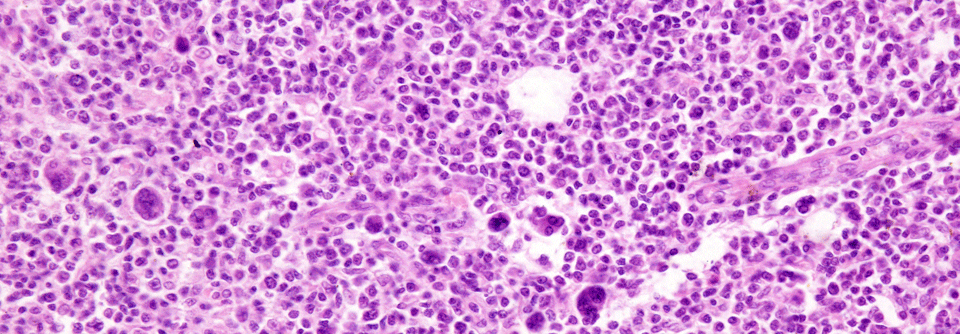

Lymphknoten einer erkrankten Person mit Hodgkin-Lymphom. Lymphknoten einer erkrankten Person mit Hodgkin-Lymphom. © JosLuis - stock.adobe.com